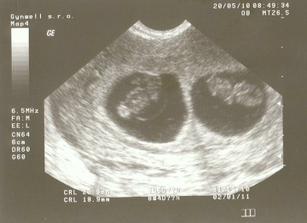

Mrňousci

Jak to všechno začalo 🙂